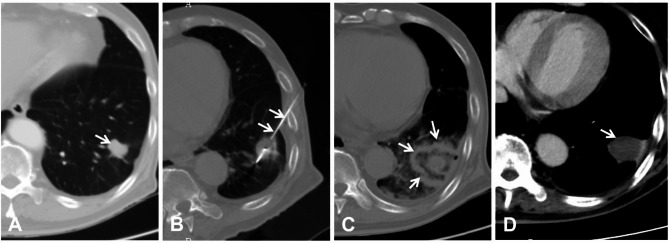

目的:评价热消融治疗肝细胞癌(HCC)肺少转移瘤(POs)的远期疗效,探讨影响预后的相关因素。方法:2012年10月至2019年1月,对62例HCC患者(男33例,女29例,平均年龄61.0岁)进行热消融治疗,治疗145个结节(平均直径2.3 cm,≤4个/例)。主要终点是无进展生存期(PFS)和总生存期(OS),次要终点是技术成功、技术疗效和并发症。采用log-rank检验和Cox比例风险回归模型分析PFS和OS。结果:技术成功率为100,技术有效率为96.8,主要并发症发生率为21%。在中位随访30个月(范围:16-50)期间,中位PFS为11.4个月(95% CI: 10.1-12.8), 1年和2年PFS率分别为43.5%和10.2%,原发性HCC的根治性治疗(P)结论:原发性HCC控制后的POs消融是安全有效的,应重视初始BCLC分期评估和根治性治疗策略。本研究存在回顾性设计、单中心数据、选择偏倚、样本量小等局限性。

Methods: From October 2012 to January 2019, 145 POs (mean diameter: 2.3 cm, ≤ 4 POs per patient) in 62 patients (male = 33, female = 29, mean age: 61.0 years old) with HCC were treated by thermal ablation. The primary endpoints were progression-free survival (PFS) and overall survival (OS), and the secondary endpoints were technical success, technical efficacy, and complications. PFS and OS were analyzed by the log-rank test and Cox proportional hazards regression models.